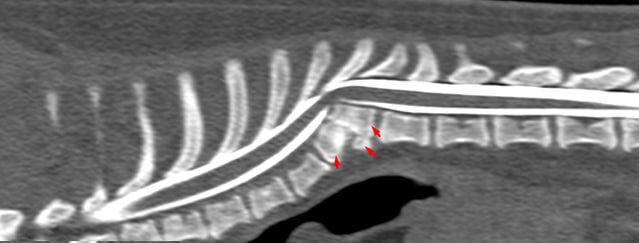

КТ (красные стрелки указывают на клиновидный позвонок Th10)

• Клиновидный полупозвонок Th10

• Кифотическая деформация угол Кобба 44,6

• Экстрадуральная компрессия спинного мозга на 35–40%, смещение его к дорсальной стенке канала.